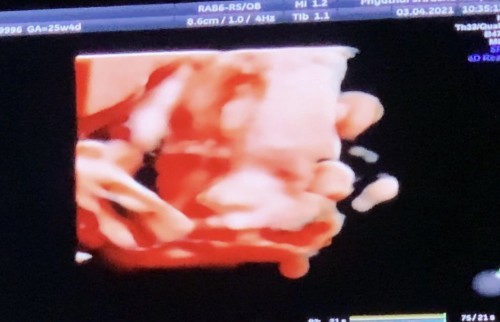

บ้านนี้ลูกสาว 25W4D จ้า พึ่งซาวด์มาวันนี้ค่ะ 3-Apr-21#ท้องแรกคะ